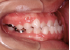

叢生 治療前 左側

いわゆる乱ぐい歯と言われていますが、八重歯もこの分類に属します。簡単に言えば、歯の大きさと顎の大きさにアンバランスがあり、並びきれないものです。形はいろいろなバリエーションがありますが、要は並びきれないので、顎を大きくするか歯を間引くかという治療方針になります。顎の骨を大きくすることもあるのですが、成長が付いて来られないとか、後戻りの危険性が大きいことなどから、歯を抜く方法が一般的です。